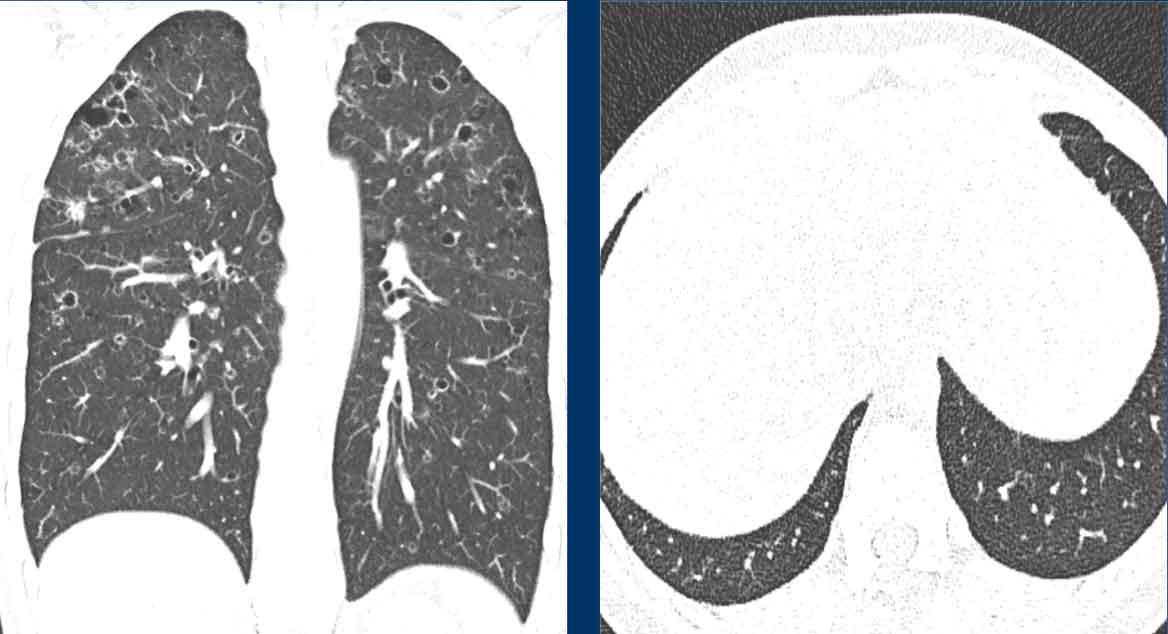

LCH – Mô Bào Tế Bào Langerhans (Langerhans Cell Histiocytosis)

Căn nguyên của Mô Bào Tế Bào Langerhans (LCH) vẫn chưa được xác định rõ, tuy nhiên hút thuốc lá đóng vai trò chủ yếu trong bệnh sinh.

Bệnh nhân có nguy cơ gia tăng mắc ung thư phổi.

LCH khởi phát dưới dạng các nốt, sau đó tạo hang và chuyển dạng thành các nang với hình dạng bất thường (nang kỳ dị, do sự hợp nhất của hai hoặc nhiều nang với nhau).

Hình ảnh

- Các nang có hình dạng kỳ dị ở một bệnh nhân nam mắc LCH.

- Trường hợp nặng của LCH giai đoạn tiến triển, hình ảnh tương tự khí phế thũng. Ở một bệnh nhân nữ không có tiền sử hút thuốc, đây cũng có thể là trường hợp LAM (bệnh cơ trơn bạch huyết) nặng.

- Nhiều nốt, một số đang tạo hang, với phân bố ưu thế ở vùng phổi trên (khác với di căn), và hoàn toàn không tổn thương các ngách màng phổi.

- Sự kết hợp giữa các nang kỳ dị, các nốt và các nốt đang tạo hang với phân bố ưu thế ở vùng phổi trên.

Đây là hình ảnh của một bệnh nhân nam 66 tuổi, có tiền sử hút thuốc lá và đến khám vì triệu chứng khó thở.

Nhận xét hình ảnh

Ghi nhận nhiều nang.

Một số có hình dạng bất thường và một số có dấu hiệu “cheerio” (hình vòng tròn) do hiện tượng tạo hang bên trong nốt (mũi tên trắng).

Ngoài ra còn ghi nhận một số nốt (mũi tên đen).

Bình luận

Sự kết hợp của các dấu hiệu này trên một bệnh nhân hút thuốc lá là điển hình cho chẩn đoán LCH.

Tiếp tục…

Trên tái tạo mặt phẳng coronal, có thể thấy rõ ràng rằng các nang chủ yếu tập trung ở thùy trên và thùy giữa, trong khi vùng đáy phổi được bảo tồn.

Đặc biệt khi LCH còn ở giai đoạn nốt, sự phân bố này có thể là dấu hiệu hữu ích trong việc phân biệt với di căn phổi, vốn có xu hướng ưu thế ở thùy dưới.

Đây là một trường hợp tương tự.

Lưu ý rằng các nang chủ yếu tập trung ở thùy trên và thùy giữa.

Các ngách màng phổi được bảo tồn.

Các nang đã gây ra tràn khí màng phổi.